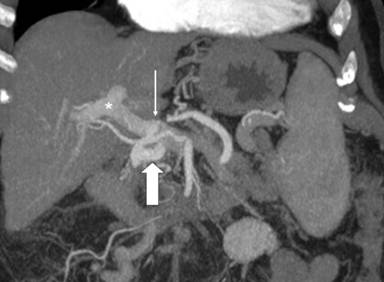

A 75-year-old female performed a quadriphasic abdominal CT examination for the characterization of a focal hepatic lesion, previously identified with a transabdominal ultrasound. Patient had a chronic HCV infection. The physical examination was substantially negative: particularly, the patient did not show any sign or symptom related to the pancreatic arteriovenous malformation or to gastrointestinal bleeding. The MDCT showed a hypervascular area of 3.5x2.5 cm in the pancreatic head, constituted of ectasic vessels (Figure 1); no calcifications were seen inside the mass. The lesion did not determine mass effect or dilation of the main pancreatic duct. During the arterial phase, there was also an early filling of the portal vein and the proximal portion of the superior mesenteric vein. Para-coronal maximum intensity projection and 3D electronic reconstructions made possible to identify the arterial afferents to the malformation (Figure 2), constituted by small aberrant branches from left gastric artery (Figure 3) and posterior inferior pancreaticoduodenal artery (Figure 4); it was also possible to identify the venous efferent drainage, constitute by the portal vein (Figure 5) and the superior mesenteric vein (Figure 6). Other MDCT findings were: presence of a cirrhotic liver with a solid 3.0x2.5 cm mass in the II segment, hyperdense in the arterial phase with washout during the portal phase, referable to hepatocellular carcinoma; an aberrant replacing right hepatic artery arising from the superior mesenteric artery; and a 1.5 cm solid hypodense lesion in the pancreatic body, with fat density and without contrast enhancement, referable to pancreatic lypomatosis.

Figure 2. 3D paracoronal maximum intensity projection arterial phase reconstruction, showing the pancreatic arteriovenous malformation (solid arrow) and their arterial afferents arising from the left gastric artery (long arrow) and the inferior posterior pancreaticoduodenal artery (short arrow). Note the improper portal venous flow toward the liver (asterisk). Ao: aorta; CA: celiac artery; CHA: common hepatic artery; GDA: gastroduodenal artery; LGA: left gastric artery; SA: splenic artery; SMA: superior mesenteric artery |

Figure 3. Maximum intensity projection paracoronal arterial phase reconstruction image shows the pancreatic arteriovenous malformation (solid arrow) and its afferents (short arrow) arising from the left gastric artery (long arrow). Note the improper early appearance of intrahepatic portal vein (asterisk). CA: celiac artery; SA: splenic artery; SMA: superior mesenteric artery |